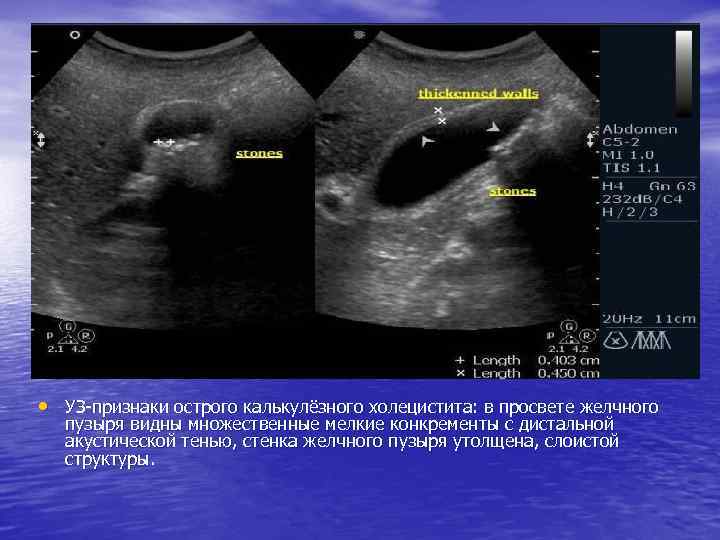

Диагностика острого холецистита • В клиническом анализе крови отмечается высокий лейкоцитоз, сдвиг лейкоцитарной формулы влево и увеличение СОЭ. УЗИ в настоящее время является основным аппаратным методом диагностики острого холецистита. В начальной стадии заболевания обнаруживают увеличение размеров желчного пузыря, утолщение его стенки. По мере прогрессирования заболевания воспалительных изменений она становится слоистой, может выявляться феномен «двойного контура» стенки, что свидетельствует о наличии деструктивных изменений Диагностическая лапароскопия, являясь инвазивным методом, применяется лишь в наиболее сложных случаях, возникающих у больных острым холециститом. Абсолютным показанием к её выполнению является ситуация, когда при наличии явных клинических проявлений острого деструктивного холецистита УЗИ не выявляет воспалительных изменений желчного пузыря. В такой ситуации клиническая картина заболевания может быть обусловлена острым аппендицитом или другим заболеванием, требующим экстренного хирургического вмешательства.

• УЗ-признаки острого калькулёзного холецистита: в просвете желчного пузыря видны множественные мелкие конкременты с дистальной акустической тенью, стенка желчного пузыря утолщена, слоистой структуры.